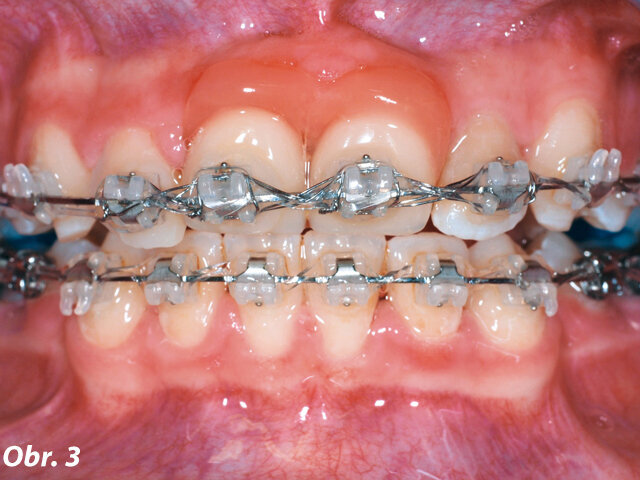

V 10 letech pacientka utrpěla trauma frontálních zubů s avulzí a replantací centrálních řezáků (zuby 11 a 21, dle značení FDI). Navzdory všem snahám nebylo možné zachovat zub 21. Předchozí zubní lékař tento zub nahradil metalokeramickým adhezivním můstkem (Marylandský můstek) (obr. 1 a 2). Naneštěstí byla v průběhu terapie potvrzena infaustní prognóza u zubu 11 – ten musel být extrahován během ortodontické léčby. Za účelem nahrazení obou centrálních řezáků byl zhotoven provizorní můstek s umělou gingivou, který byl připevněn na fixní ortodontické aparáty (obr. 3).

Obr. 3: Fotografie během ortodontické léčby s dočasnou náhradou centrálních řezáků (Obr. 1–3 publikovány se svolením prof. A. Wichelhause)